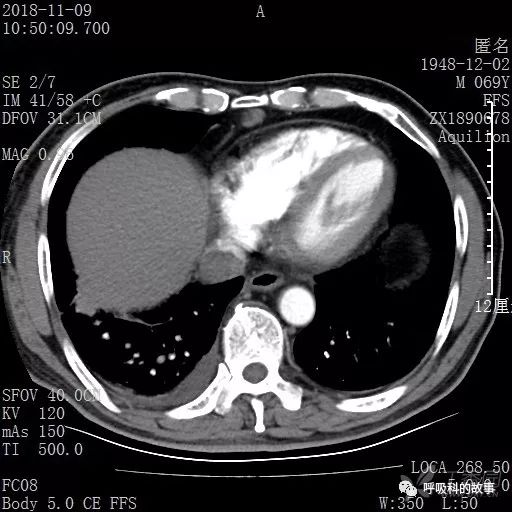

胸部增强CT示右肺门占位伴远端阻塞性肺炎,纵膈、右肺门、右侧颈根部、右侧腋下及肝门部肿大淋巴结。两侧胸腔少量积液。

肺窗CT